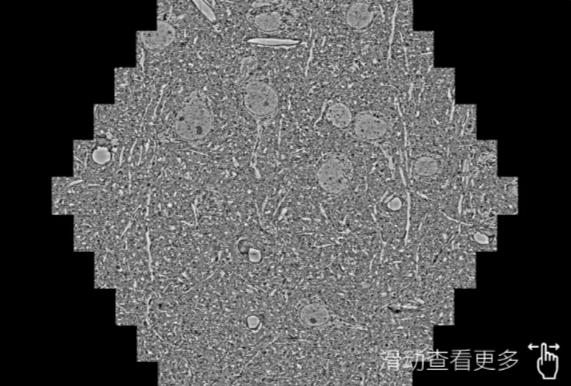

鼠脑切片。左图使用牡丹江蔡司牡丹江扫描电镜MultiSEM706对165μmx143pm面积区域成像,耗时仅需1.5秒。右图为鼠脑切片中30μm区域放大效果。样品由芝加哥大学B.Kasthuri提供。

使用蔡司高速牡丹江扫描电镜MultiSEM对1mm²人脑皮层组织进行高分辨成像,并对其中的各种细胞结构进行三维重构分析。左图展示了2x3mm²组织平面中锥体神经元的三维重构效果。右图显示了局部体积神经元三维重构。图像由哈佛大学chtman实验室提供,渲染图由D. Berger 制作。